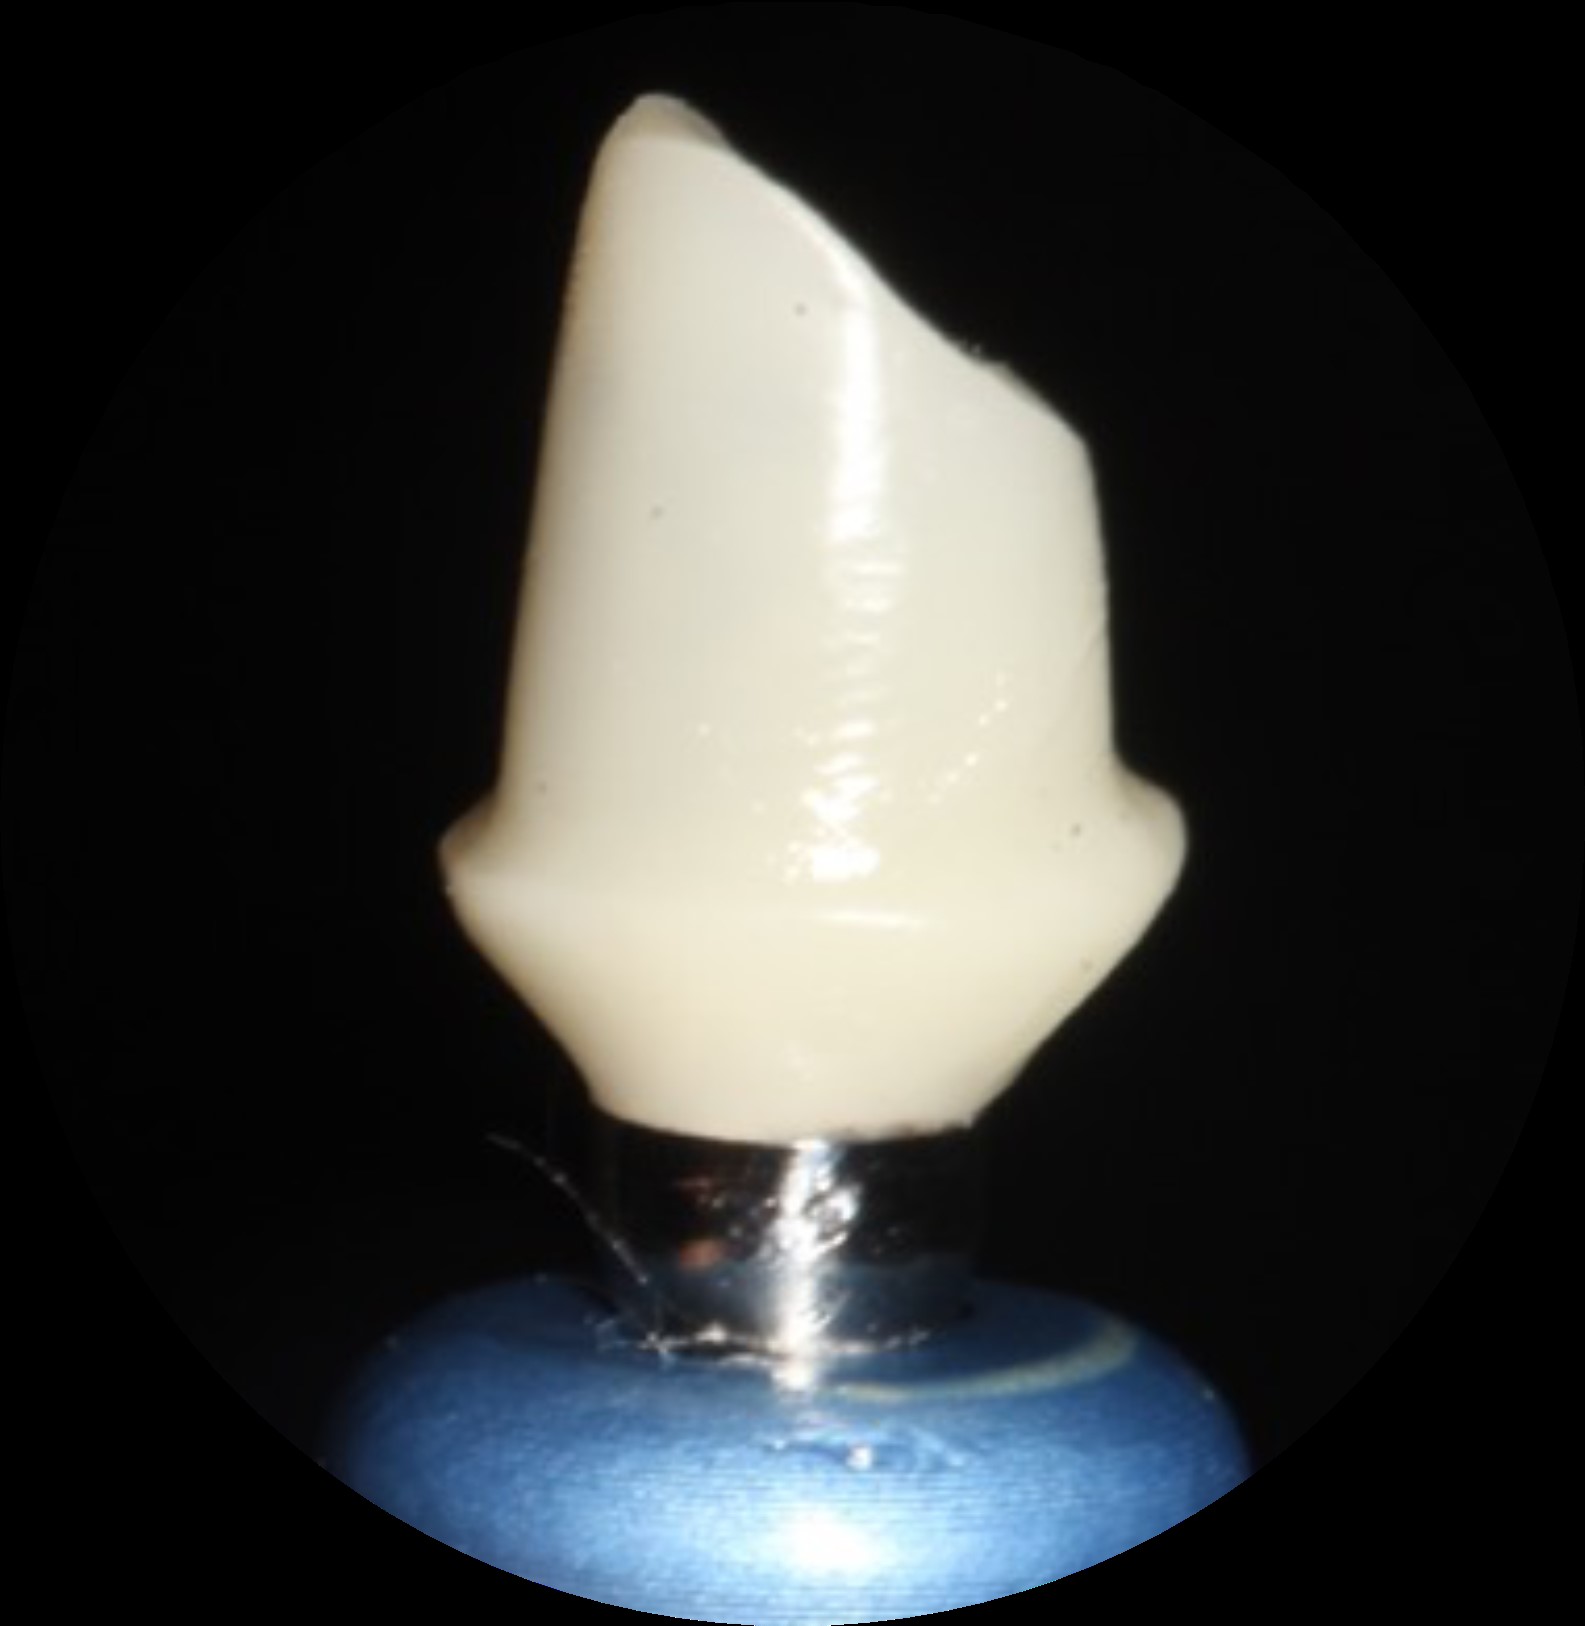

Pasul 3 – Procesul de fabricare a pilonului de vindecare personalizat

Rotește inelul superior al matriței până când forma/ dimensiunea dorită a puțului de silicon este aliniată la inserția protetică VPI dorită, prezentă în baza matriței.

Poziția fiecărei inserții de conexiune protetică VPI în interiorul bazei matriței ar trebui să fie disponibilă pe fișa informativă care însoțește kitul matriței. Acest lucru va facilita procesul de identificare a poziției inserțiilor de conectare de tip implant pentru asistent.

Pasul 4 – Procesul de fabricare a pilonului de vindecare personalizat

Asistentul instalează un bont temporar în puțul matriței cu codul corespunzător (E.g pS) la cel din fila de formă anatomică a ghidului (E.g pS).

El / Ea introduce apoi materialul compozit adecvat în spațiul deschis și vindecă ușor cu unul sau mai multe trepte.

Apoi dezinstalează bontul personalizat de vindecare creat și continuă cu lustruirea suprafeței compozite și dezinfectarea corespunzătoare.

Procesul de fabricare a bontului de vindecare personalizat se poate face după programarea consultației sau chiar la o intervenție chirurgicală, deoarece necesită doar aproximativ 4 minute pentru a fi finalizată.